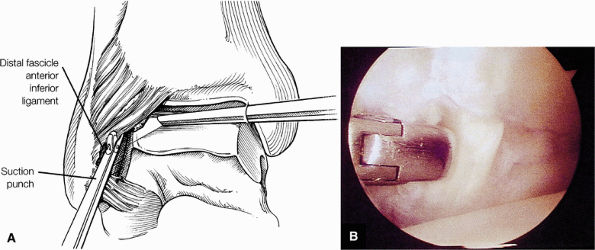

FIGURE 5.59 ● (A) The inferior tibiofibular joint is a fibrous joint. (B) Arthroscopic view of the right ankle demonstrates the syndesmotic ligament and the trifurcation. The trifurcation includes the fibula in the background with the tibia superior and the talus inferior. Approximately 20% of the ligament is intra-articular, and it runs at a 45° angle from the tibia to the fibula.